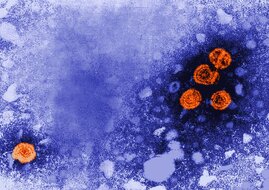

Eine Impfstoffplattform, mit der sich im Mausmodell eine sehr gute immunologische Antwort (B- und T-Zellantwort) und ein Schutz gegen Hepatitis B…